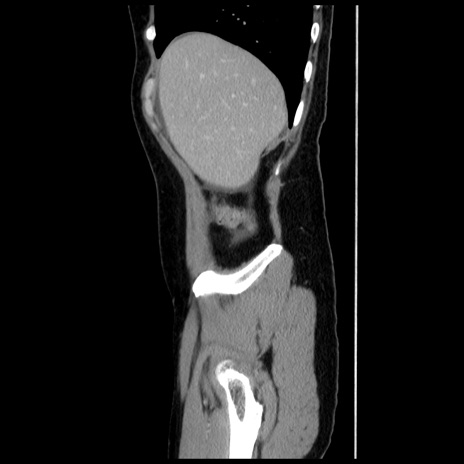

横断像

【症例】 50歳代女性

【主訴】 腹痛

【現病歴】前日生レバーを食べた。今朝に排便あり。 昼前に突然発症の腹痛を生じ、当院救急外来を受診した。

【既往歴】 子宮筋腫にてで子宮全摘後

【身体所見】 意識清明、腹部:平坦、軟、下腹部やや左を中心に圧痛・反跳痛あり、筋性防御あり

【データ】WBC 7800、CRP 0.07